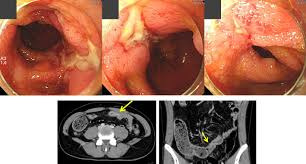

🔍 크론병, 그냥 장염 아닙니다 (핵심 차이)

✔ 입~항문 전체 염증 가능

✔ 장 ‘표면’이 아니라 장벽 깊숙이 손상

👉 장이 계속 망가지는 만성 염증 질환

심해지면

- 장이 좁아지고

- 고름 생기고

- 장 막히고

- 결국 장 절제 수술